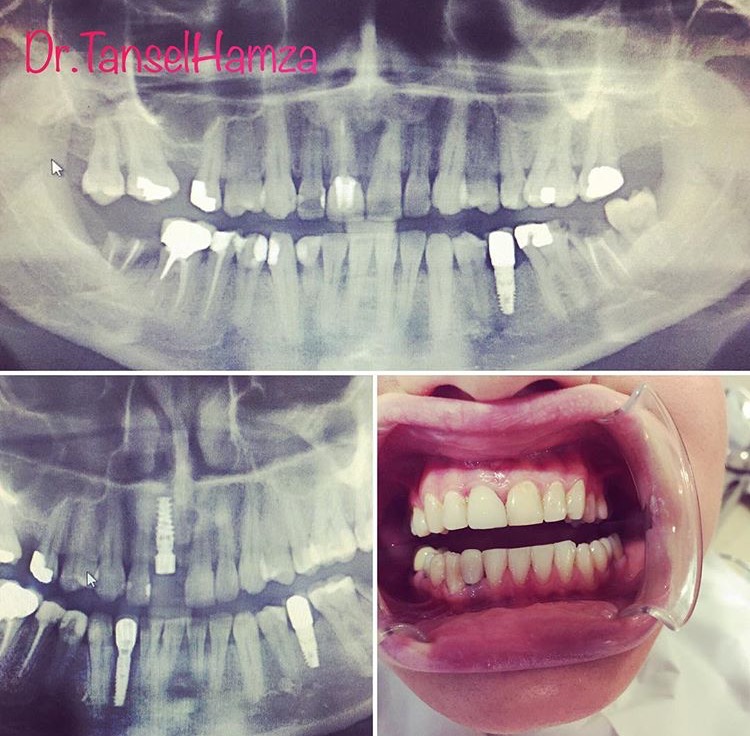

Tansel Hamza

Diş Estetiği ve İmplant (Bölüm 3)